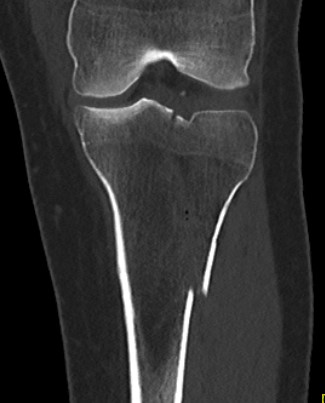

CT scan

Assess joint line

- predetermine fracture pattern before fixation

- will pick up medial condyle / bicondyle / metaphyseal fractures not seen on xray